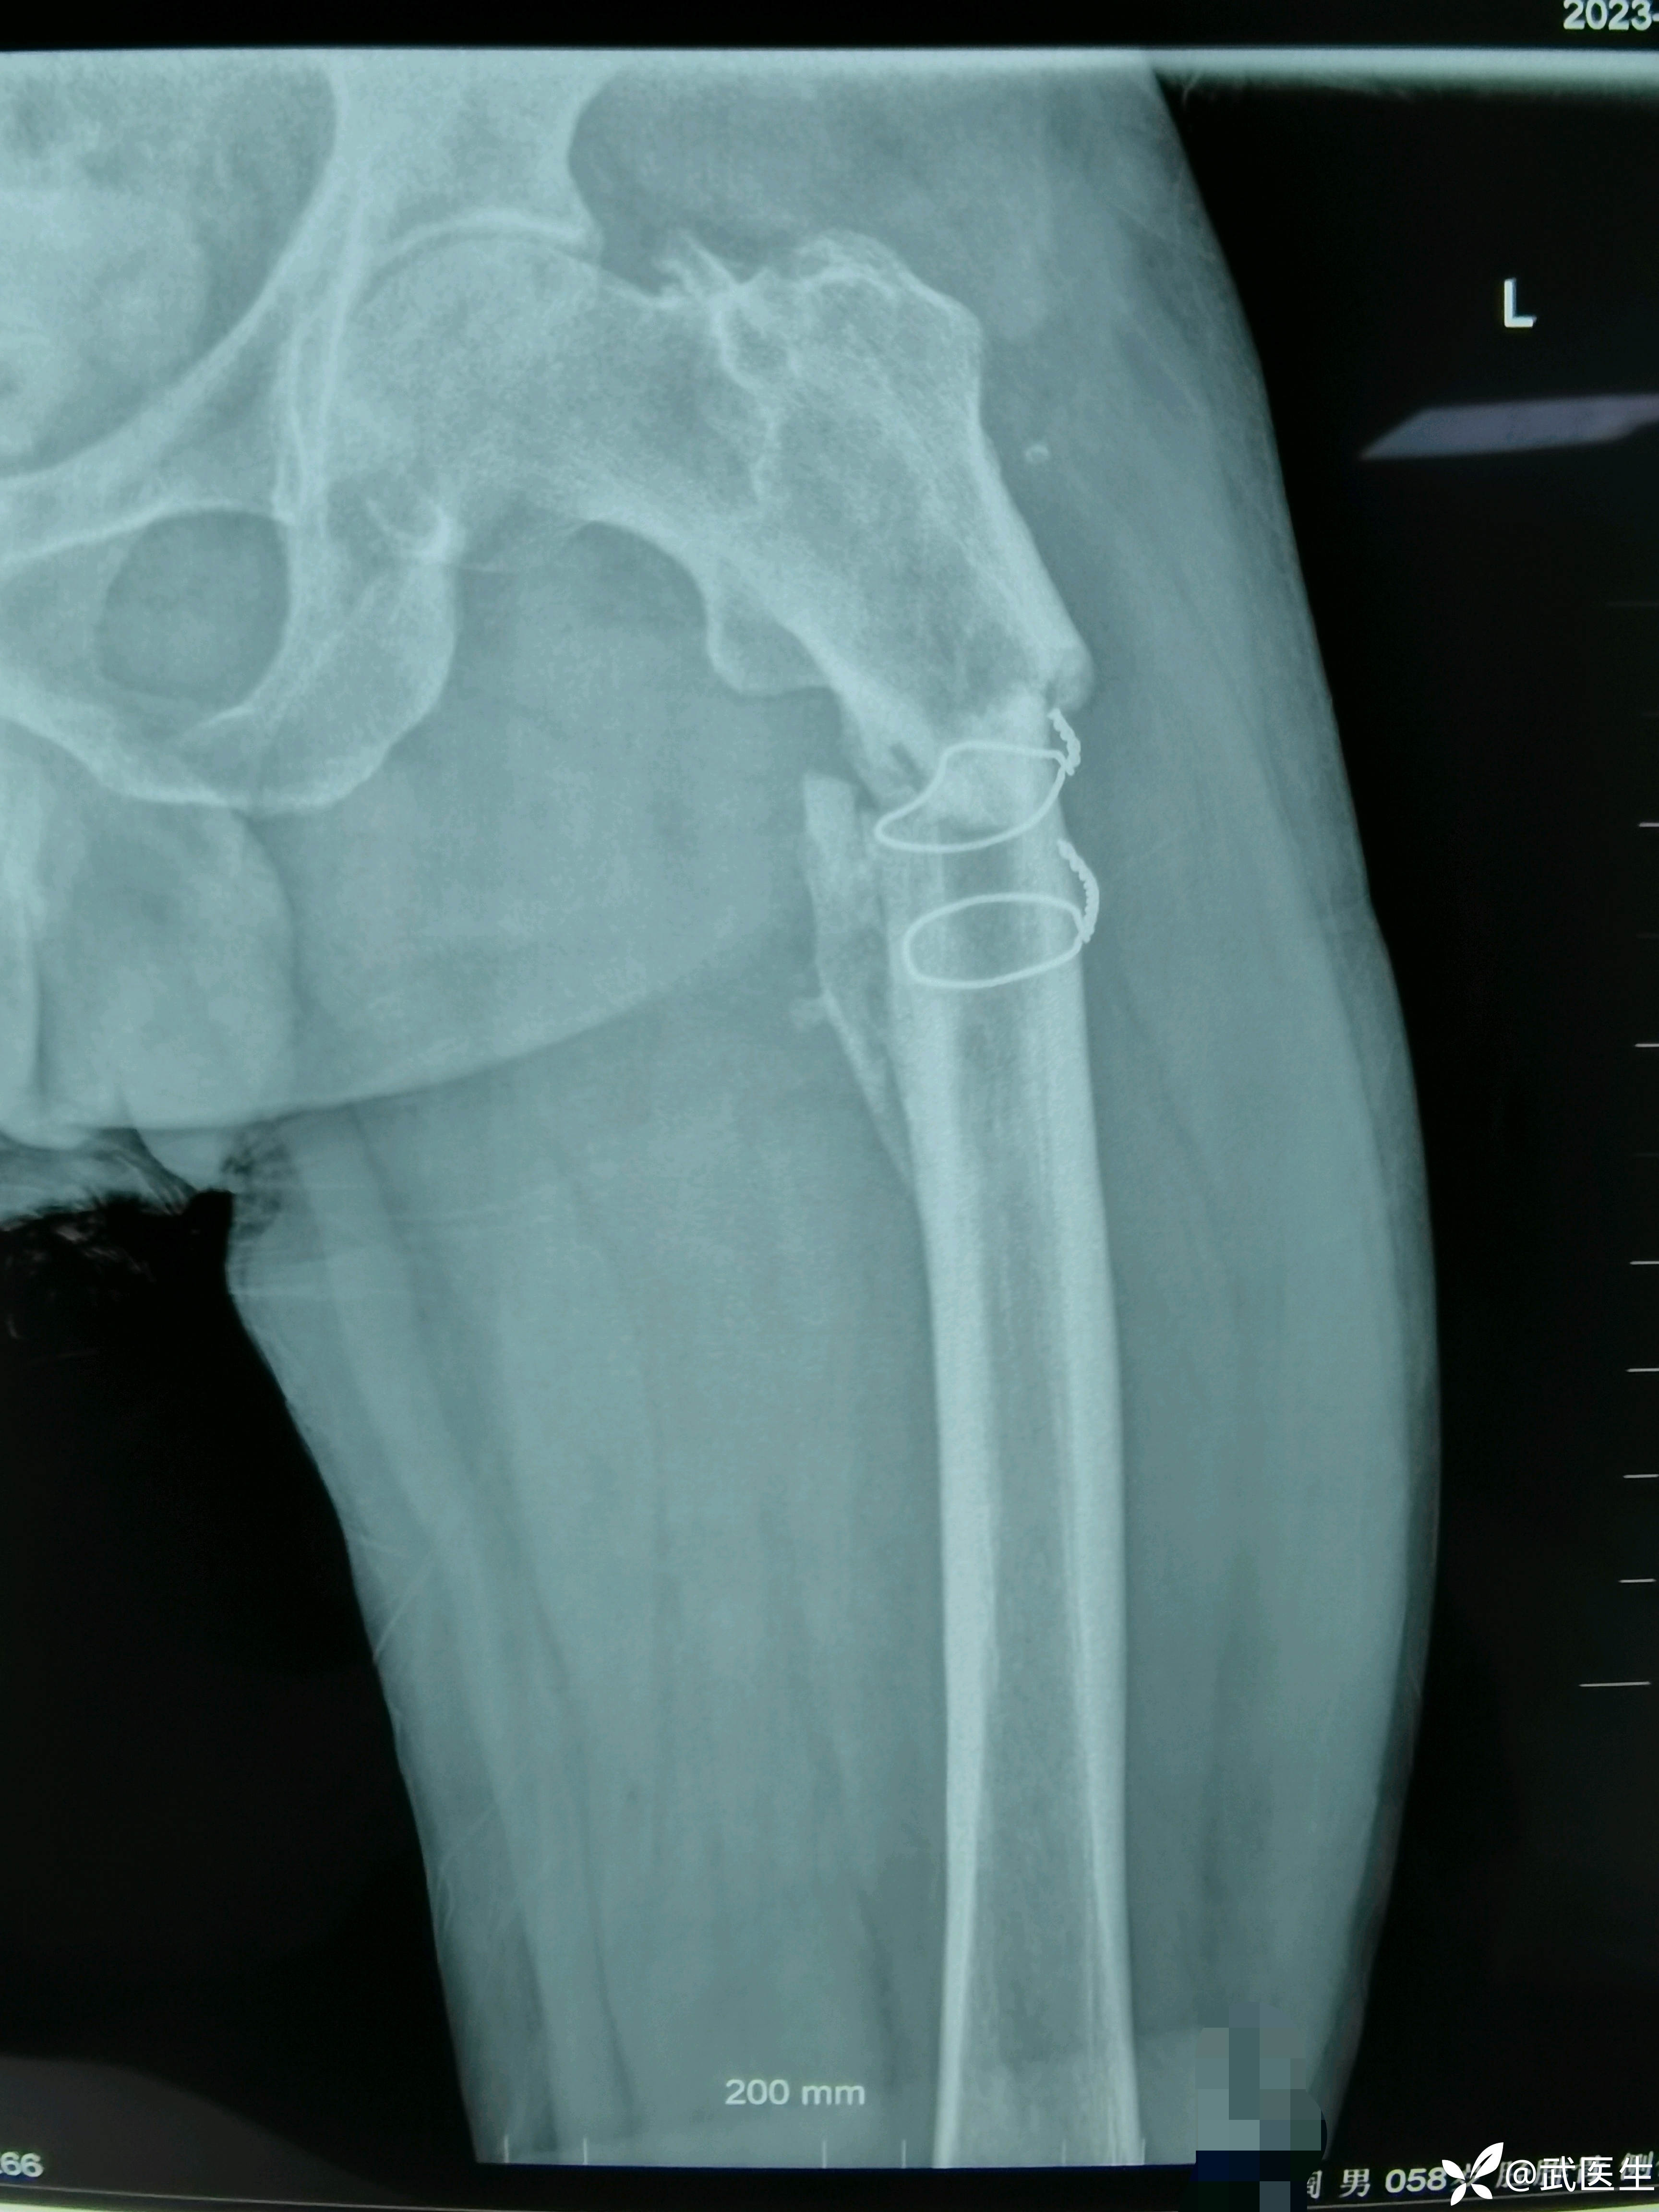

男,58岁,路滑摔倒致左髋疼痛活动受限一小时就诊,片子如下

患者二十年前本院因股骨近端骨折手术治疗,于术后两年取出内固定,钢丝未取出。